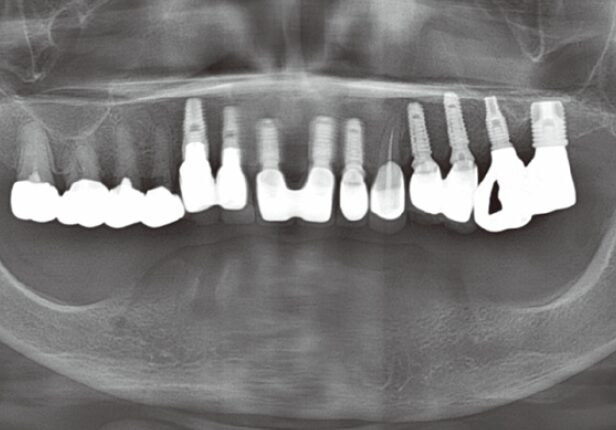

Panorâmica pós-cirurgia

Panorâmica Final da Coroa

Panorâmica Pós-Cirúrgia